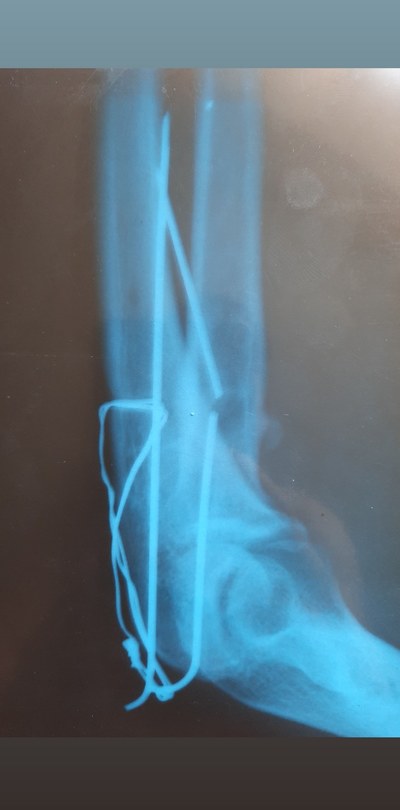

И вот три месяца назад стал жутко болеть этот палец, думаю видимо туфли неудобные купила. Но палец с каждым днем стал распухать просто жесть. Пришла я в травмпунк, мне доктор говорит "вы наверно стукнулись об угол мебели вот он и болит, ну ладно давайте я вам рентген сделаю". Я жду когда он мне результат скажет, а он выбегает злой и орёт на меня, мол "Вы почему врете то, иголку загнали в ногу и пришли как будто не знаете". Я в шоке, в голове каша, стало плохо и страшно. Столько лет иголка в ноге жила. Самое интересное что половина эта была с ушком, тобишь толстая половина иглы. Как она 16 лет сидела в ноге ума не приложу. И ведь не беспокоила ни разу. Сейчас от неё осталось напоминание в виде небольшого шва. Хируг сказал что повезло нереально как, игла была между костью и сухожилием, и воздух не попал, поэтому и не беспокоила. Вот такая история🤭